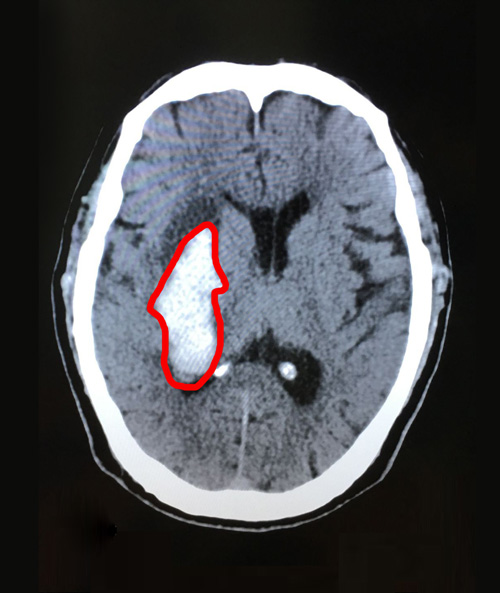

檢查結(jié)果出來后,右側(cè)基底節(jié)區(qū)腦出血,出血量一度達(dá)到35毫升,非常危險!

術(shù)前影像:右側(cè)基底節(jié)區(qū)急性腦出血,右側(cè)腦室后角少量積血